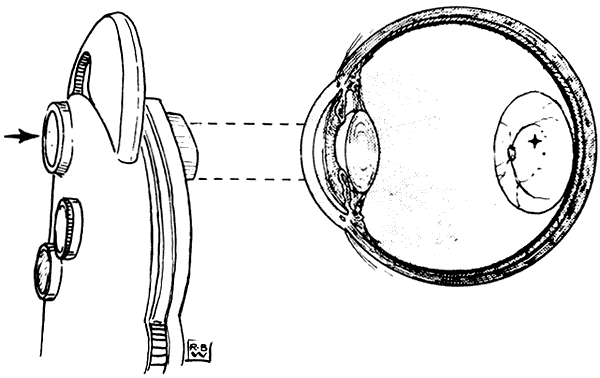

Less marked and relatively steady eccentricity of fixation (a few degrees or less of visual angle) is common and can be detected by the clinician with various tests. Visuscopic devices (no longer available as separate instruments, but simulated by some direct ophthalmoscopes that provide a selection of viewing apertures) project directly onto the retina an image of a target or a small object that can be fixated by the patient (Fig. 11). By comparing the position of this image with that of the foveolar light reflex, the examiner can estimate the degree of eccentric fixation.

Fig. 11. The Visuscope. (Von Noorden GK, Maumanee AE. Atlas of Strabismus. 2nd ed. St Louis: CV Mosby, 1973:81.)